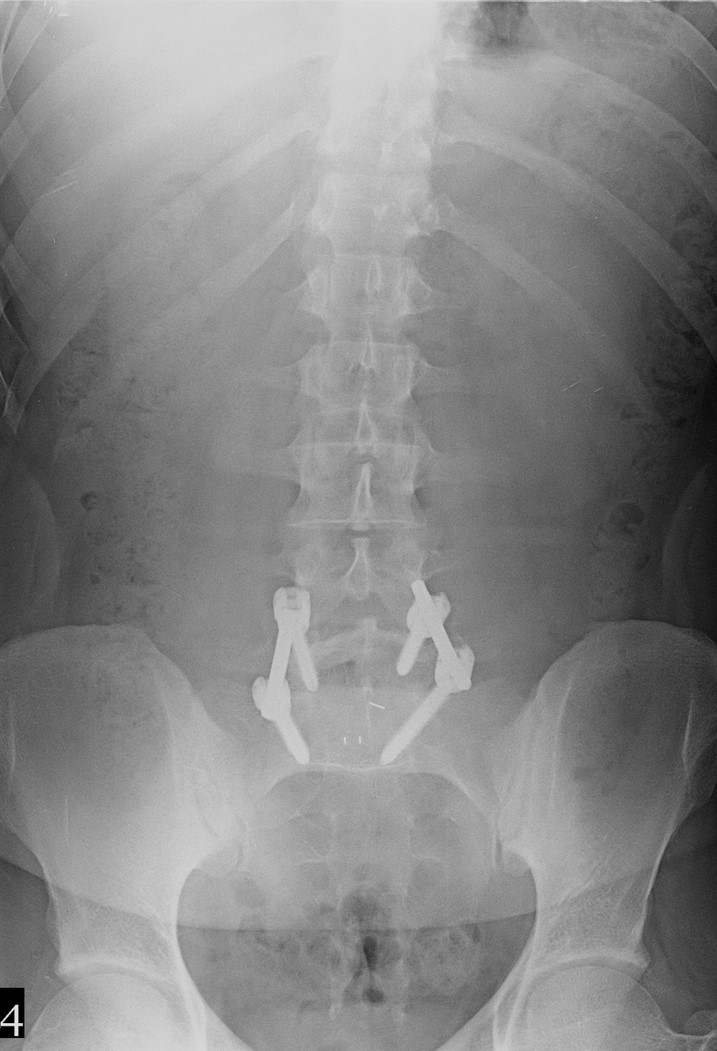

34 Yaşında Erkek Hasta

Low back pain

ODİ: %16

RM: 5/24

Ameliyat Sonrası